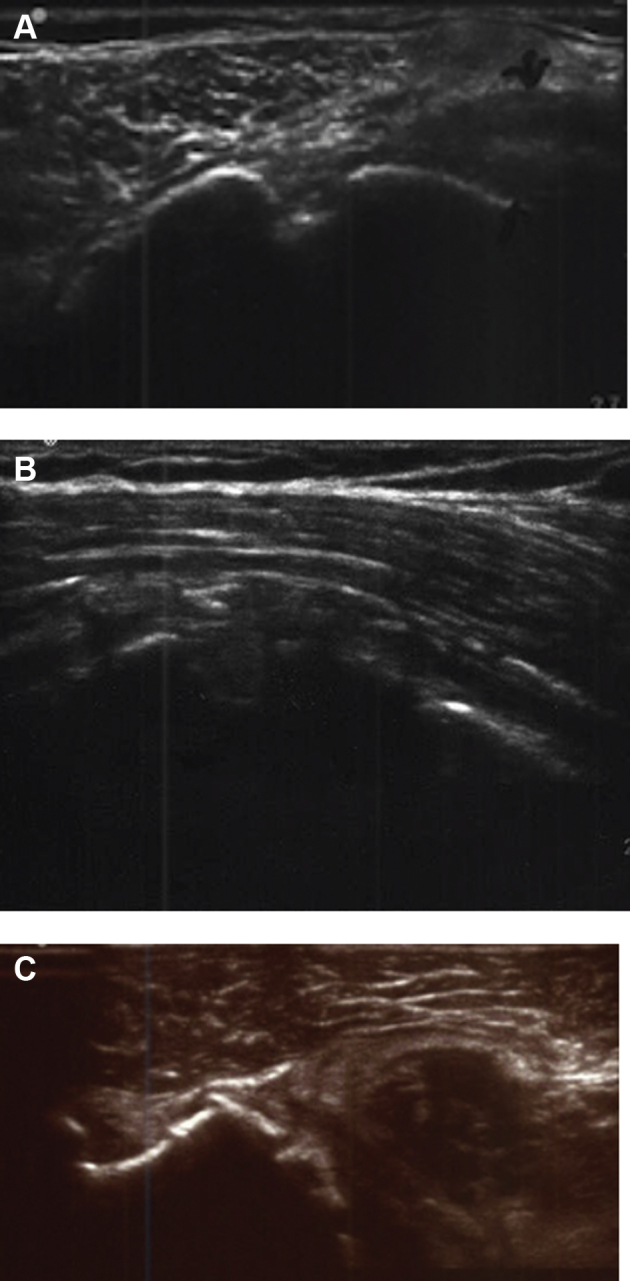

On the operative shoulder, ultrasound examination revealed 16 intact, normal-appearing subscapularis tendons. The subscapularis tendon of 4 shoulders was noted to be abnormal (3 partial-thickness tears and 1 full-thickness tear) (Fig. 2). The ultrasound examination of the contralateral, nonoperative shoulder demonstrated 18 normal tendons and 2 abnormal tendons (1 partial-thickness tear and 1 full-thickness tear).

Figure 2.

Ultrasound images demonstrating a (A) normal, (B) attenuated, and (C) full-thickness tear in postoperative RTSA shoulders.